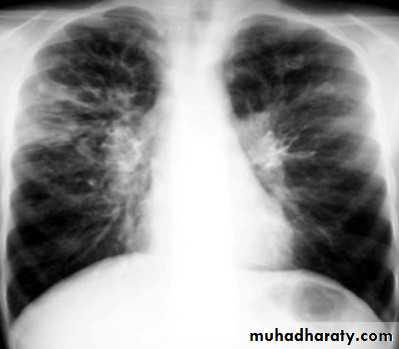

Plain radiograph

Chest x-rays are usually abnormal

1. Tram-track opacities are seen in cylindrical bronchiectasis, and

2. air-fluid levels may be seen in cystic bronchiectasis.

Honey comb shadow

3.Overall there appears to be an increase in bronchovascular markings, and bronchi seen end on may appear as ring shadows .

4.Pulmonary vasculature appears ill-defined, thought to represent peri bronchovascular fibrosis .